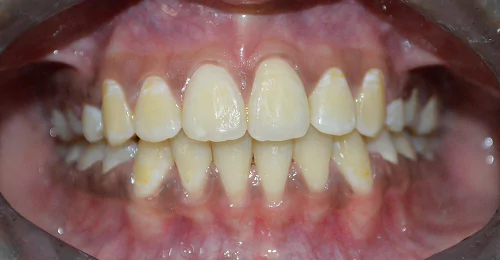

Orthodontic Case – III

(Case Done by Dr. Sonali Deshmukh M.D.S. / Orthodontist )

Deep – II Correction

Pre Treatment